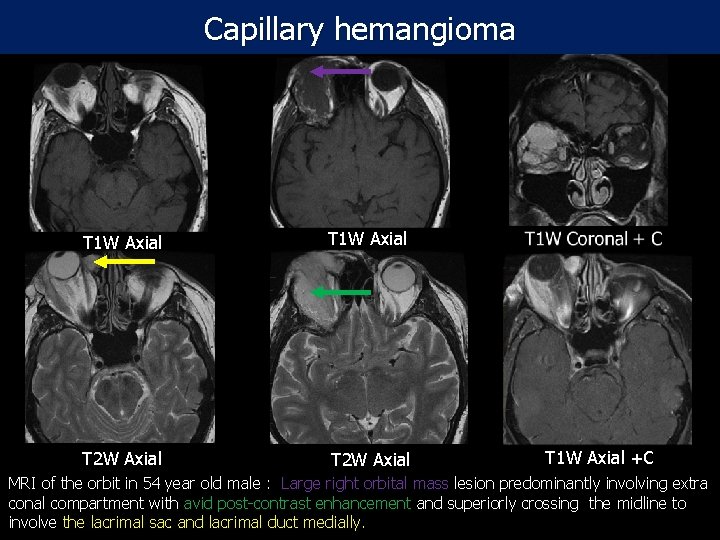

Capillary hemangioma T 1 W Axial T 2 W Axial T 1 W Axial +C MRI of the orbit in 54 year old male : Large right orbital mass lesion predominantly involving extra conal compartment with avid post-contrast enhancement and superiorly crossing the midline to involve the lacrimal sac and lacrimal duct medially.